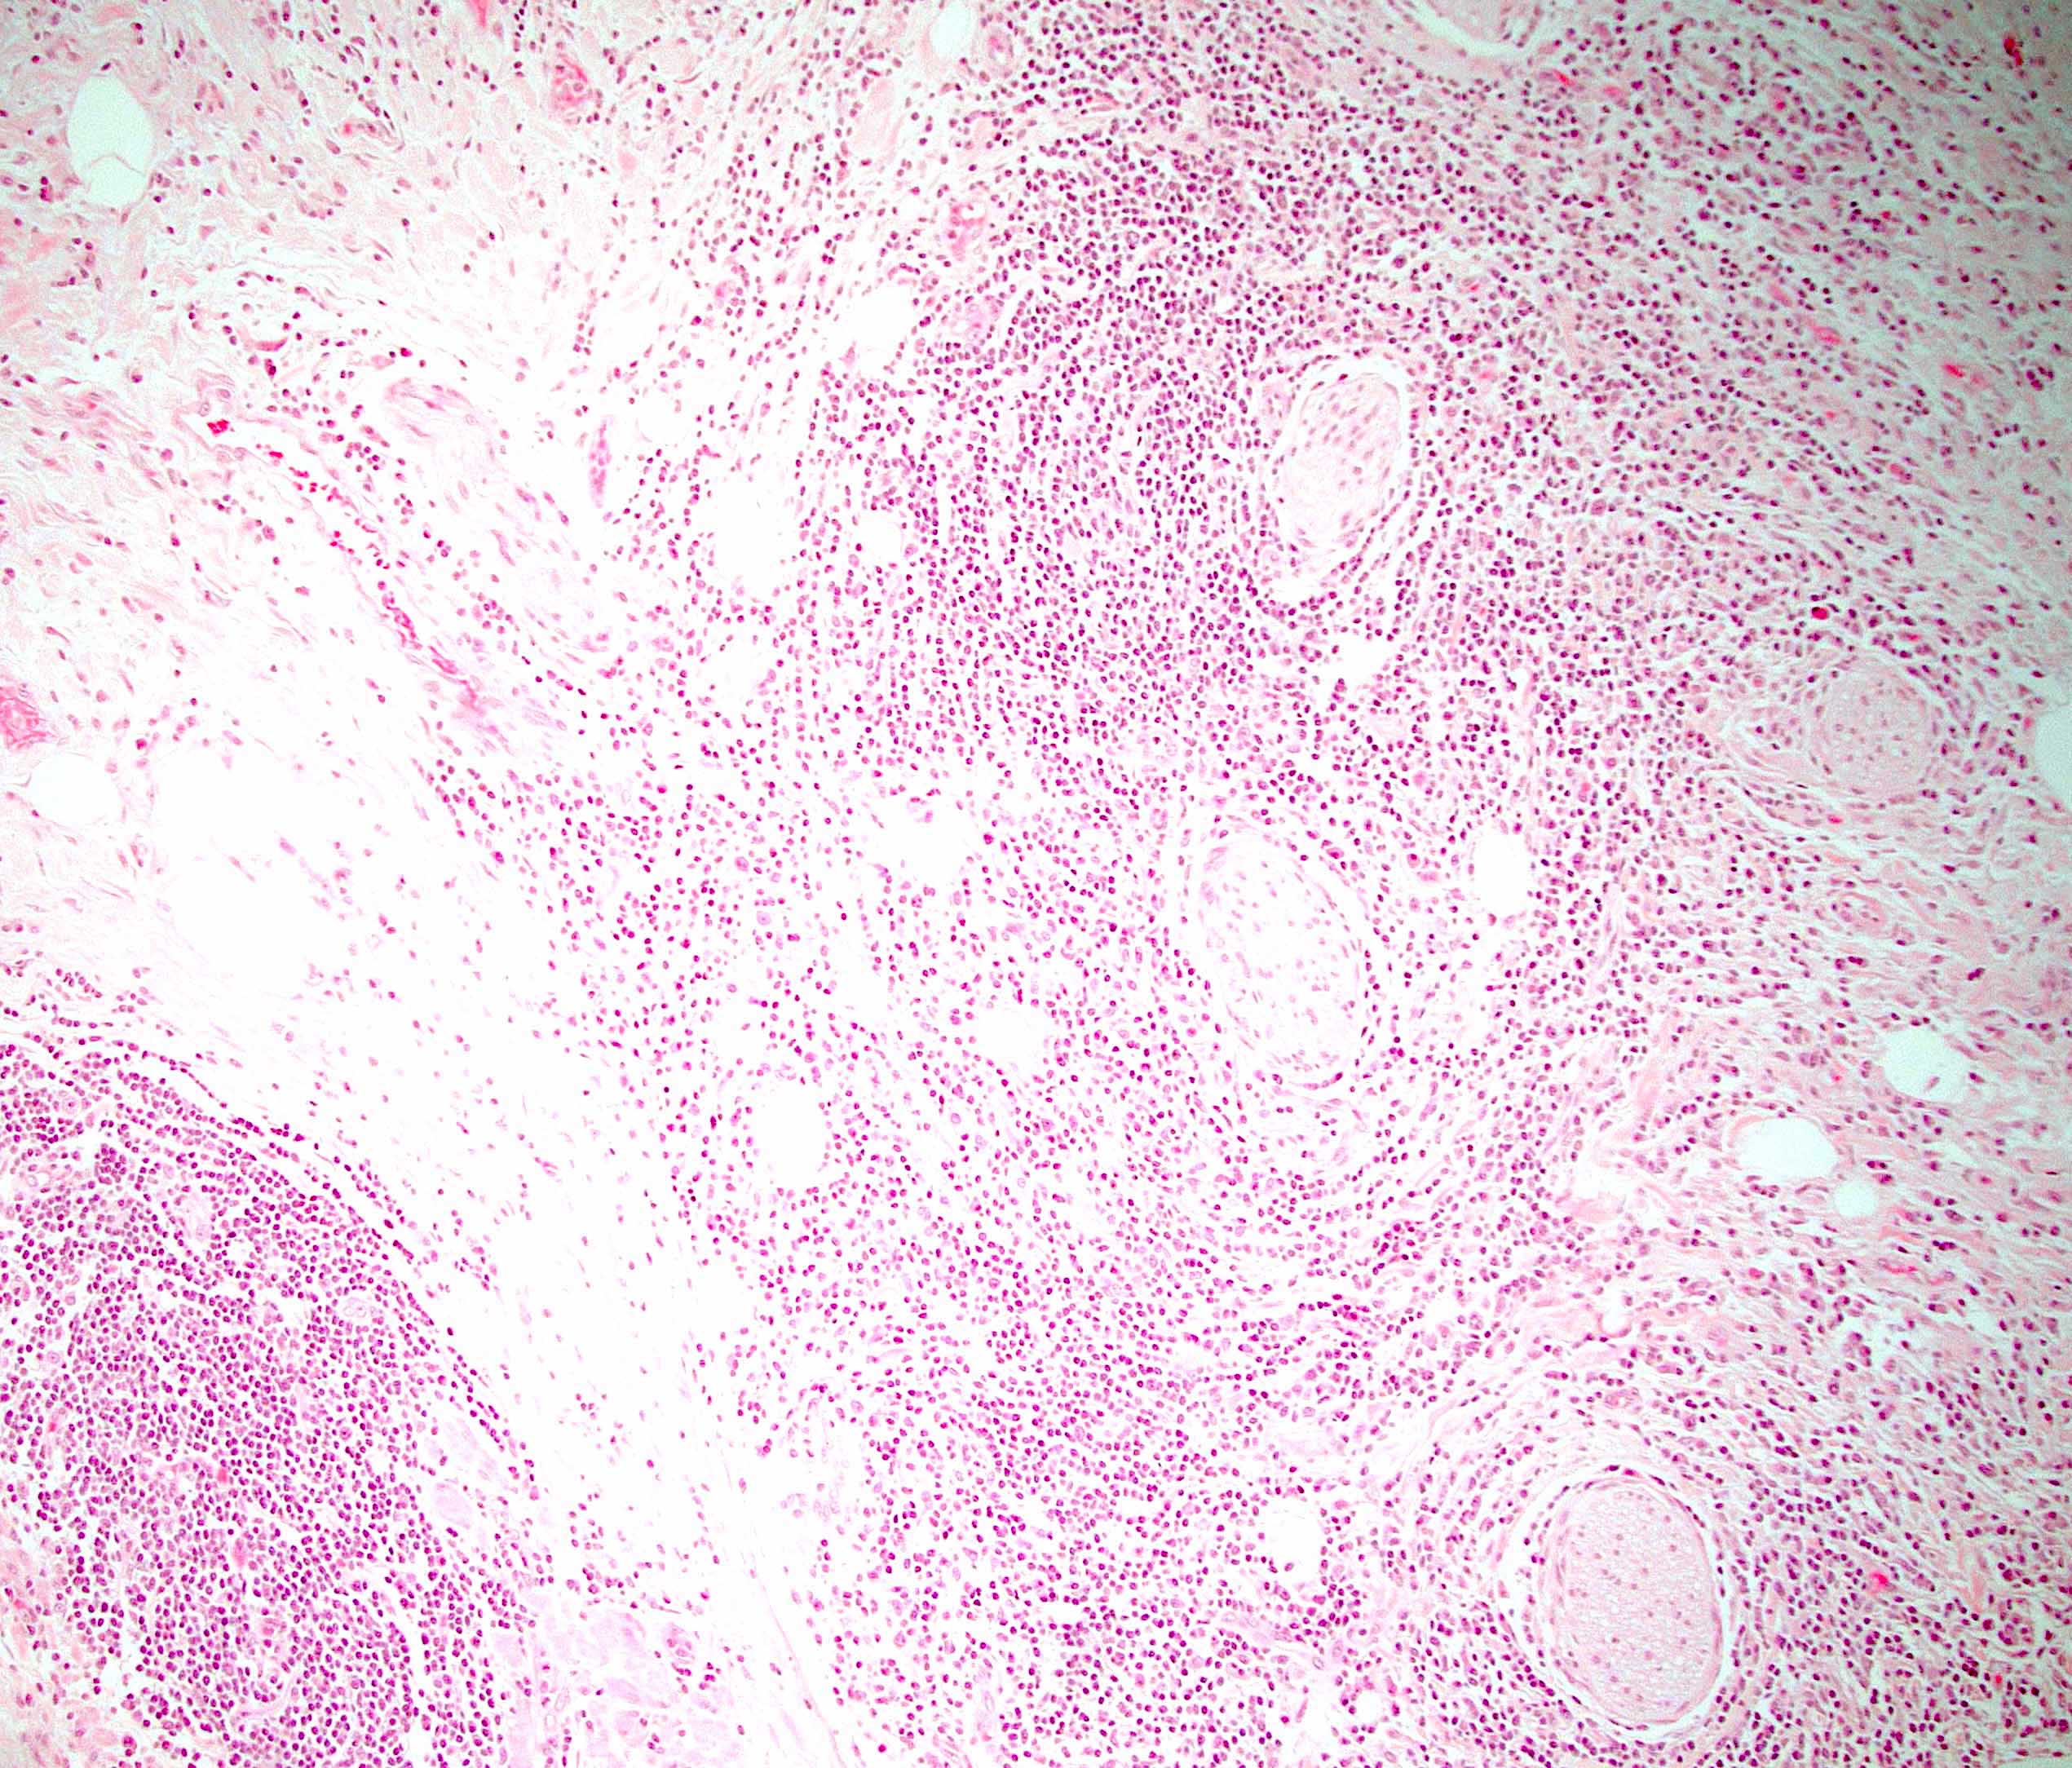

Microscopic (histologic) description

- Characteristic findings (at least 3 for level 1 criteria) (Pancreas 2011;40:352)

- Periductal lymphoplasmacytic infiltrate without granulocytic infiltration

- Obliterative phlebitis

- Storiform fibrosis

- Abundant (> 10 cells/high power field) IgG4 positive plasma cells

- Biopsy showing some but not all of the above features can be used as supportive evidence for the diagnosis of autoimmune pancreatitis (Pancreas 2011;40:352)

- Inflammation is localized within the pancreatic parenchyma and is centered around / within medium to large interlobular ducts, which causes shrinkage of the ductal lumen (Pathologica 2020;112:197)

- Inflammation can also be seen between the pancreatic parenchyma and peripancreatic adipose tissue (Pathologica 2020;112:197)

- Inflammation of the venous wall can progress to obliterative phlebitis with fibrosis of the lumen (Pathologica 2020;112:197)

- As the inflammation progresses, fibrosis becomes more diffuse, assuming a whorled or storiform pattern (Pathologica 2020;112:197)

- Perineural inflammation can also be present (Pathologica 2020;112:197)

Microscopic (histologic) images

- Follicular pancreatitis:

- Inflammation with numerous lymphoid follicles with or without prominent germinal centers

- Lacks storiform fibrosis, obliterative phlebitis and IgG4+ cells